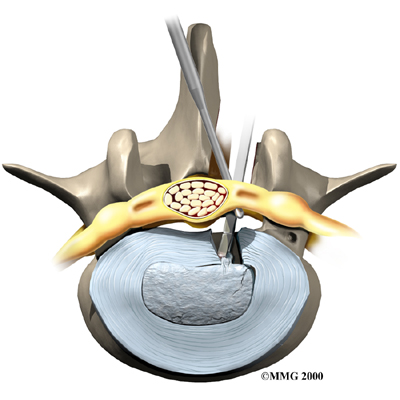

Microdiscectomy

Microdiscectomy is becoming the standard surgery for lumbar disc herniation. The procedure is used when a herniated disc is putting pressure on a nerve root. It involves carefully taking out part of the problem disc (discectomy). By performing the operation with a surgical microscope, the surgeon only needs to make a very small incision in the low back. Categorized as minimally invasive surgery, this surgery is thought to be less taxing on patients. Advocates also believe that this type of surgery is easier to perform, that it prevents scarring around the nerves and joints, and that it helps patients recover more quickly.

Related Document: FYZICAL Heber Valley's Guide to Lumbar Discectomy